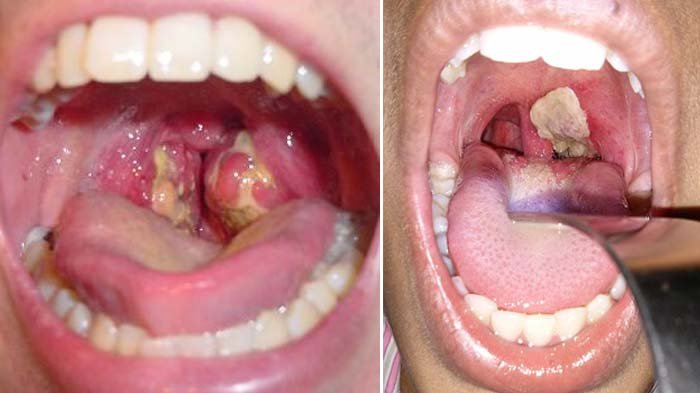

Untuk menghindari infeksi, jauhkanlah berbagai penyebab terjadinya radang tersebut. Bronkitis, radang pada cabang tenggorokan akibat infeksi. Penyebab radang tenggorokan adalah infeksi bakteri infeksi virus atau reaksi alergi tubuh terhadap alergen. 1122015 bronkhitis merupakan gangguan pada cabang batang tenggorokan akibat infeksi. Hasil penelitian ilmuwan dari hongkong menyebutkan bahwa varian omicron berkembang biak 70 kali lebih cepat daripada varian delta di saluran udara manusia atau bronkus. Penyakit tenggorokan akan sangat mempengaruhi makan dan komunikasi pasien.

Bronkhitis merupakan gangguan pada cabang batang tenggorokan akibat infeksi. Di atas adalah kunci jawaban tema 2 kelas 5 halaman 81 82 pembelajaran 5 subtema 2 pentingnya udara bersih bagi pernafasan. Untuk menghindari infeksi, jauhkanlah berbagai penyebab terjadinya radang tersebut. Radang cabang tenggorokan ini adalah komplikasi biasa dari campak, demam berdarah, batuk rejan, flu, demam tipus dan penyakit infeksi lainnya. Rinits juga dapat terjadi karena reaksi alergi terhadap perubahan cuaca, serbuk sari, dan debu.

Penderita mengalami demam dan banyak menghasilkan lendir yang menyumbat batang tenggorokan. Batuk berdahak dapat terjadi karena adanya infeksi pada saluran nafas, seperti influenza, bronchitis, radang paru, dan sebagainya. Jika alat ini terganggu karena penyakit atau kelainan maka proses pernapasan akan terganggu, bahkan dapat menyebabkan kematian. Penyakit radang pada bronkus disebut bronkitis. 1122015 bronkhitis merupakan gangguan pada cabang batang tenggorokan akibat infeksi.

Hello health group tidak menyediakan saran medis, diagnosis, atau perawatan. Penyakit radang pada bronkus disebut bronkitis. 1122015 bronkhitis merupakan gangguan pada cabang batang tenggorokan akibat infeksi. Selain infeksi, radang tenggorokan juga bisa menjadi gejala beberapa penyakit. Gejalanya adalah penderita mengalami demam dan menghasilkan lender yang menyubat batang tenggorokan.